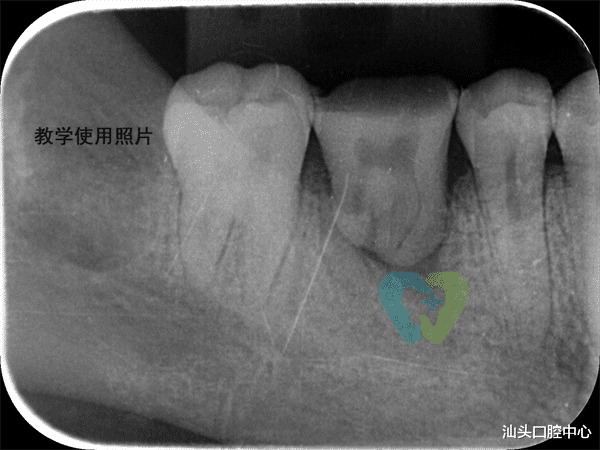

移植后的智齿

要注意哪些事情?术后24小时别刷牙、别漱口,吃温凉的软食,避免用移植牙咬东西;按时吃消炎药,别抽烟喝酒,防止感染;自体牙移植并非百分百能成功,如果智齿牙根有炎症、缺牙区骨头不够,可能会失败,得提前和医生沟通清楚。